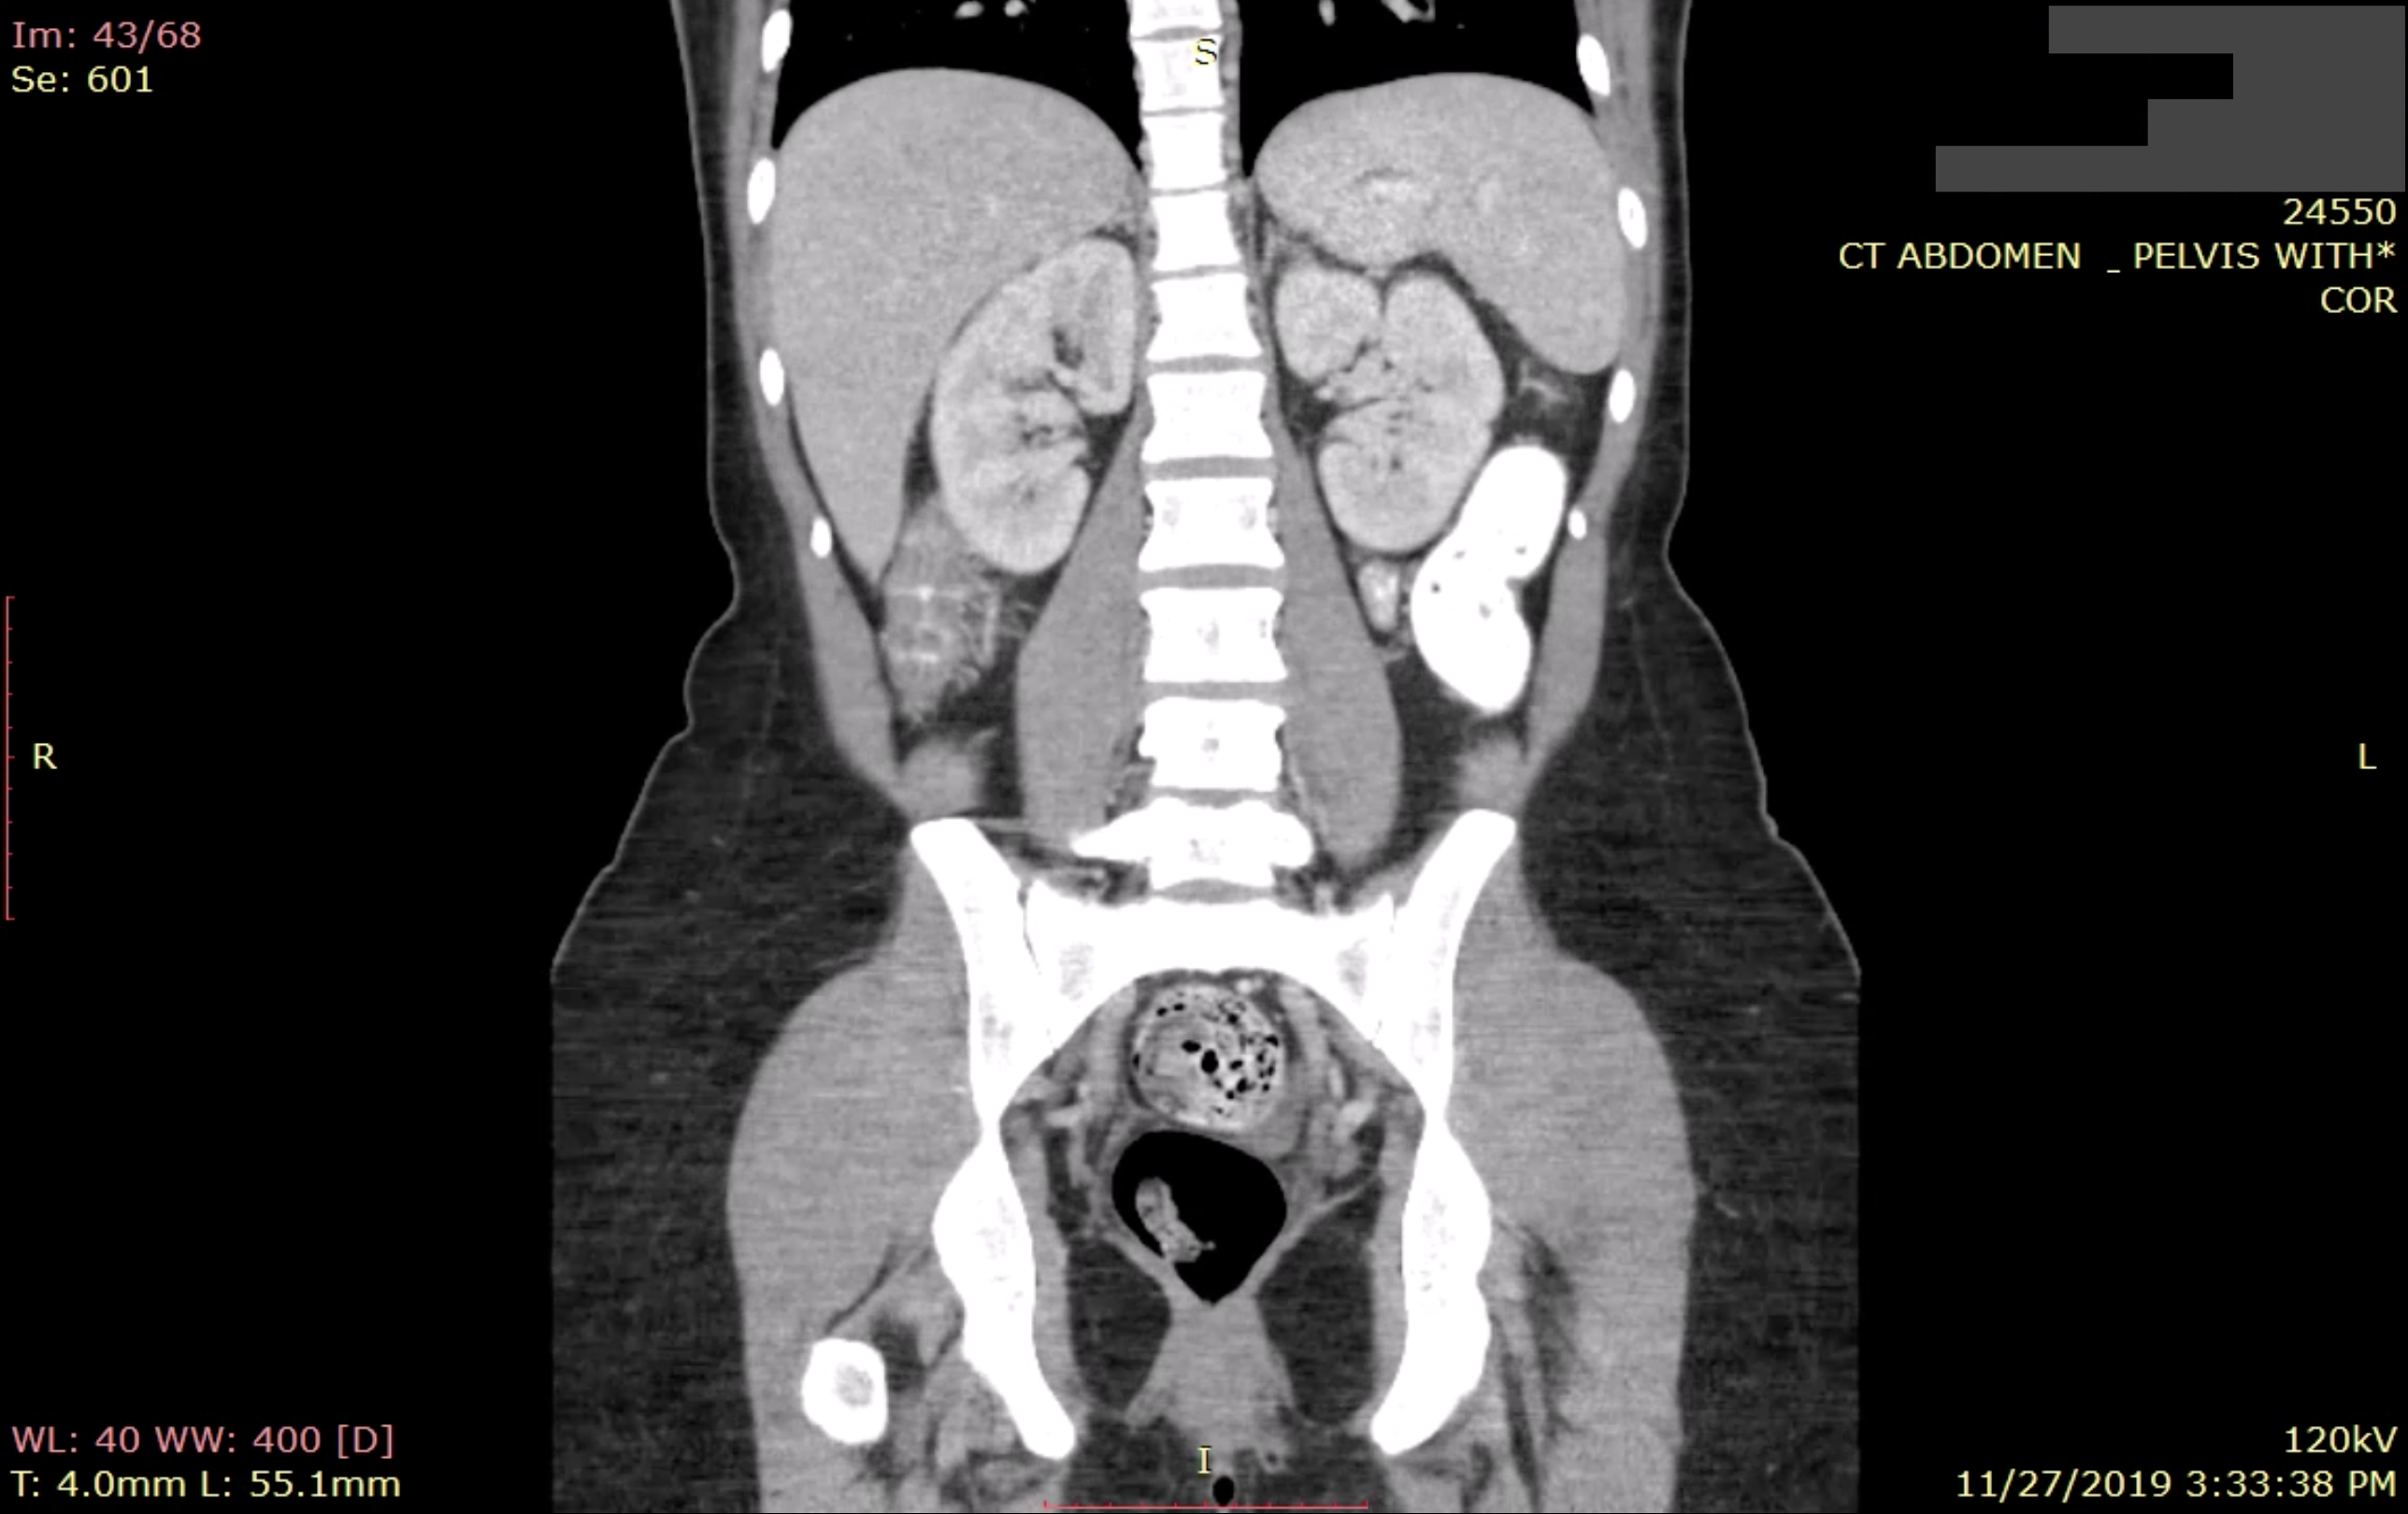

About half of all the exposed images, which include X-rays, ultrasounds and CT scans, belong to patients in the United States.

A decades-old file format and industry standard known as DICOM was designed to make it easier for medical practitioners to store medical images in a single file and share them with other medical practices. DICOM images can be viewed using any of the free-to-use apps, as would any radiologist. DICOM images are typically stored in a picture archiving and communications system, known as a PACS server, allowing for easy storage and sharing. But many doctors’ offices disregard security best practices and connect their PACS server directly to the internet without a password.

These unprotected servers not only expose medical imaging but also patient personal health information. Many patient scans include cover sheets baked into the DICOM file, including the patient’s name, date of birth and sensitive information about their diagnoses. In some cases, hospitals use a patient’s Social Security number to identify patients in these systems.

As part of our investigation, we found a number of U.S. imaging centers storing decades of patient scans.

One patient, whose information was exposed following a visit to an emergency room in Florida last year, described her exposed medical data as “scary” and “uncomfortable.” Another with a chronic illness had regular scans at a hospital in California over a period of 30 years. And one unprotected server at one of the largest military hospitals in the United States exposed the names of military personnel and medical images.

But even in cases of patients with only one or a handful of medical images, the exposed data can be used to infer a picture of a person’s health, including illnesses and injuries.